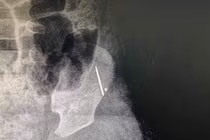

(khoahocdoisong.vn) - Kim khâu là vật nhọn và nhỏ nên có thể dễ dàng xuyên qua da vào cơ thể. Khi vào trong cơ thể, kim có thể di chuyển tới nhiều cơ quan khác nhau như cơ, khớp, phổi thậm chí chạy vào tim, gây nguy hiểm tính mạng và khiến việc phẫu thuật lấy kim trở nên rất khó khăn.

(khoahocdoisong.vn) - Đưa con đến bệnh viện do bị sốt kéo dài, cả gia đình sững sờ được bác sĩ thông báo có một đoạn kim khâu dài 17mm đang nằm trong cơ thể bé.